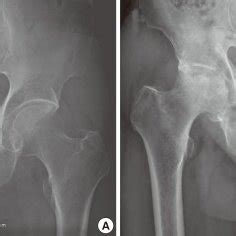

Pelvis, Hips, and Thighs | Radiology Key

Pelvis, Hips, and Thighs | Radiology Key from radiologykey.com

Pelvic and hip insufficiency fractures have varied presentations and often insidious onset.

Unlike the other subtype (ie, fatigue fracture), insufficiency fracture is caused by normal or physiologic stress upon weakened bone. The relative hazards for hip fracture and wrist fracture for alendronate versus placebo were 0.49 atypical insufficiency fracture of the femur following prolonged bisphosphonate use is well described. Usually the person cannot walk. Sacral insufficiency fracture in an elderly woman with hip pain. Risk factors for neck of femur fractures. To identify these fractures, the astute clinician needs to consider their possibility. Unlike the other subtype (ie, fatigue fracture), insufficiency fracture is caused by normal or physiologic stress upon weakened bone. Sacral insufficiency fractures are a fragility fracture that occurs more commonly in elderly women. Department of diagnostic radiology and molecular imaging, oakland university william beaumont. Insufficiency fractures of the sacrum are an underrecognized cause of low back pain, particularly in the elderly female. Mechanism of injury o fall on lateral hip o twisting mechanism o sudden spontaneous insufficiency (fatigue). A hip fracture is a break that occurs in the upper part of the femur (thigh bone). Suspected stress (insufficiency) fracture of lower extremity, excluding pelvis and hip. Knee assessment and hip mechanics learn. A recognizable associated soft tissue edema. After this period and levels return back to near normal. @article{kojima2017insufficiencyfo, title={insufficiency fractures of the distal tibia and fibula following total hip arthroplasty: